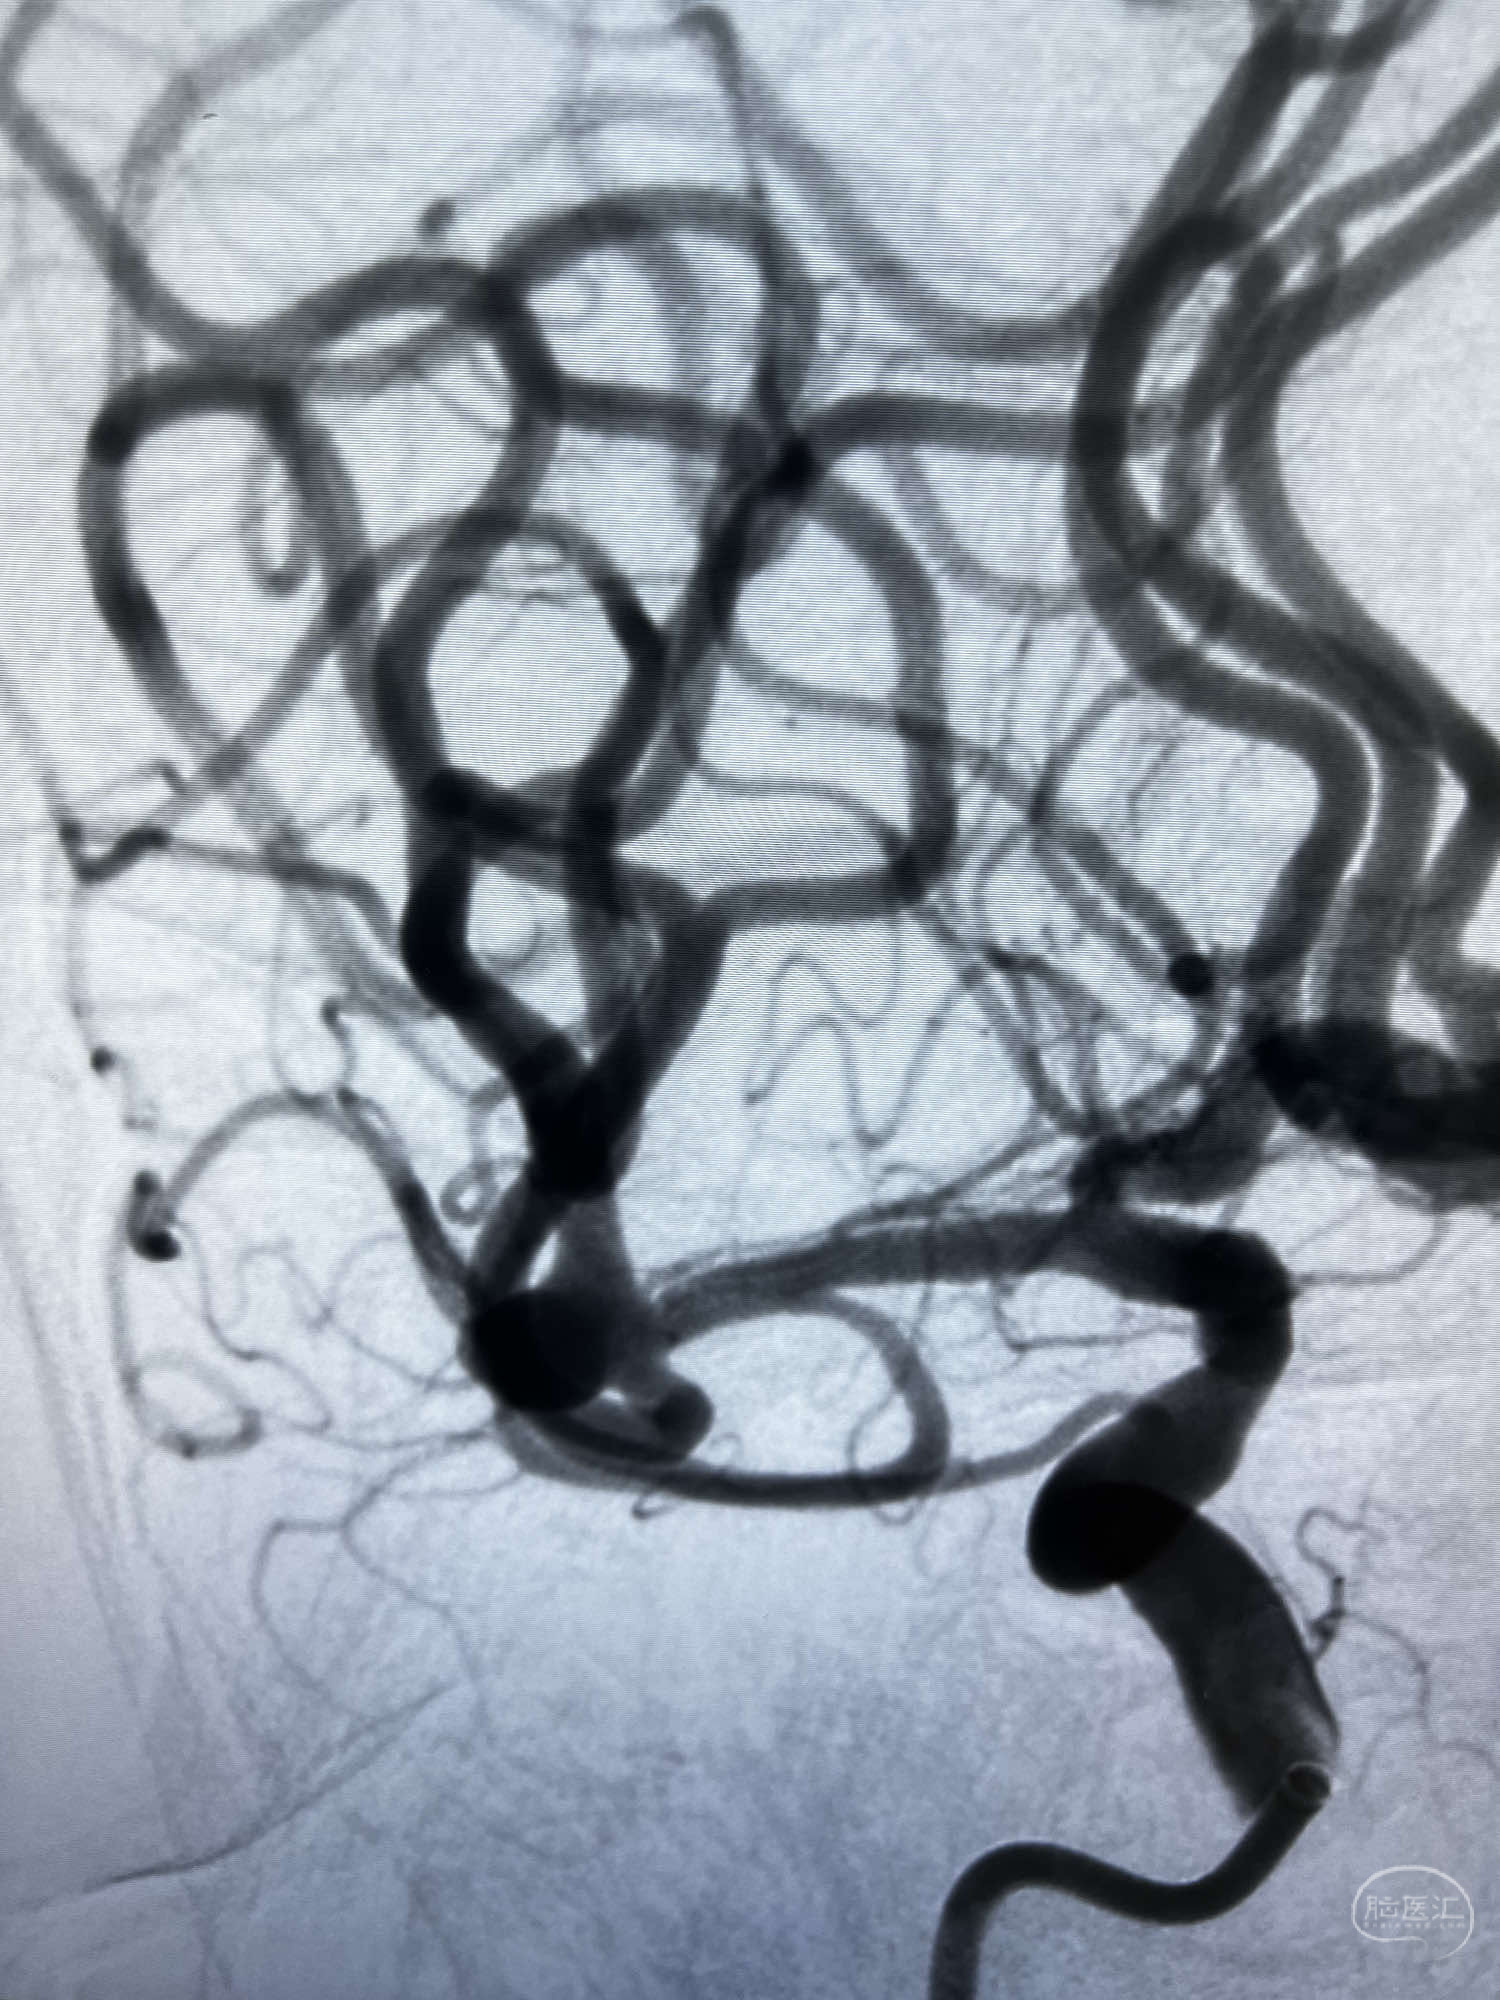

DSA示:左侧颈内动脉眼动脉段以远闭塞,后交通动脉开放,椎基底动脉通过后交通动脉代偿左侧大脑中动脉区域,右侧发出双侧大脑前动脉,右侧大脑中动脉M1末端宽颈动脉瘤,大小约4.3mmx4.6mm。

6F Neuromax➕6F115cm 心玮中间导管建立路径,sychro14微导丝➕VIA21超选至动脉瘤体内近中部,WEB5mmx3mm植入动脉瘤。

WEB瘤内扰流装置5mmx3mm经过“种子、萌芽、开花”三个阶段,打开后良好贴壁,动脉瘤内血液滞留,载瘤动脉通畅。WEB一步到位,通过瘤内扰流的方式起到栓塞动脉瘤的作用,避免了应用支架保护分支血管,简化了操作步骤,降低了术中血栓及出血的风险。